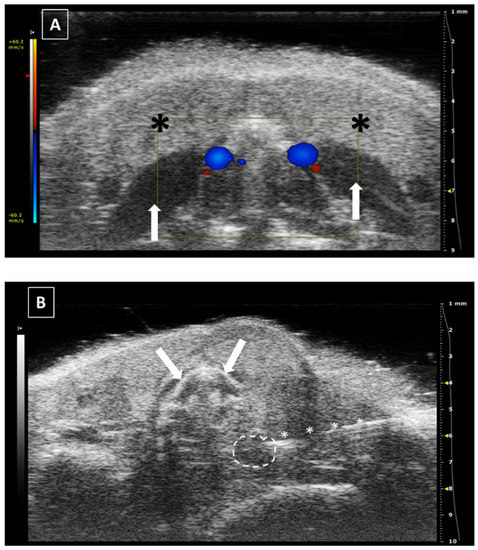

The intrahepatic injection is an easy procedure due to the size of the liver, which allows us to inject in both left and right sides of the organ. In our opinion, the right approach is easier due to the presence of the stomach on the left, which reduces the space for maneuvering. The animal is placed in ventral recumbency and hair is shaved in the cranial part of the abdomen. After localizing the desired region of the liver, the needle is moved under and parallel to the probe from the outside and into the abdomen, avoiding the rib bones. We will see a hyperechoic line going into the hypoechoic and homogeneous hepatic tissue. The injection can be confirmed with the appearance of an anechoic structure (the injected fluid) inside the liver tissue. After injecting, the needle should be kept in place for some seconds. Later, it can be removed and the organ should be examined for the presence of hemorrhages. An example of a liver injection is shown in Figure 4.

The recommended maximum volume of injection depends on the size of the organ, but in the literature, we can find volumes around 40–50 microliters [28,29,30]. An excess in the injection volume could lead to a rupture of the hepatic tissue due to a pressure increase in the tissue and this will lead to the appearance of an acute local hemorrhage, or even an hemoabdomen in case the rupture affects the Glisson’s capsule.

3.4. The Spleen

The spleen is a hypoechoic hematic organ, typically located on the left side of the abdomen, caudal to the stomach and lateral to the left kidney, but it can slide around the cranial part of the abdomen, especially during splenomegaly [25,26]. Due to this reason, the approach for its injection will depend on where it is located. In its usual place, a lateral approach is the best and easiest way of injecting. The animal should be placed in lateral recumbency, with the left side up. After shaving the hair, the scanning probe is placed over the last ribs and slowly displaced caudally. The spleen will appear on top of the screen, just under the skin. We will slightly balance the probe ventrally without losing sight of the structure and will insert the needle from the back of the animal. In a standardized view, the needle will arise from the right side of the screen and go medially. If the pressure from the ultrasound probe is enough, the spleen will be immobilized between it and the needle, and the injection will be performed easily. Similar to the liver, the maximum injected volume depends on the organ size but in previously published work we can find a range from 20 to 50 microliters [31]. After a few seconds, the needle can be removed and a last exam for the absence of bleeding should be performed. A representative image of the injection is shown in Figure 5.

Figure 4. Intrahepatic injection. (A) Right side approach. Needle is marked with white asterisks. (B) Left side approach. Injected fluid is marked with white arrows. The fluid appears as an anechoic collection inside the homogeneous hypoechoic liver tissue. Images obtained at 40 MHz frequency.

Figure 5. Intrasplenic injection. Needle is marked with white asterisks and the spleen is surrounded by a dashed line. Stomach can be localized due to its typical acoustic shadow. Images obtained at 40 MHz frequency.